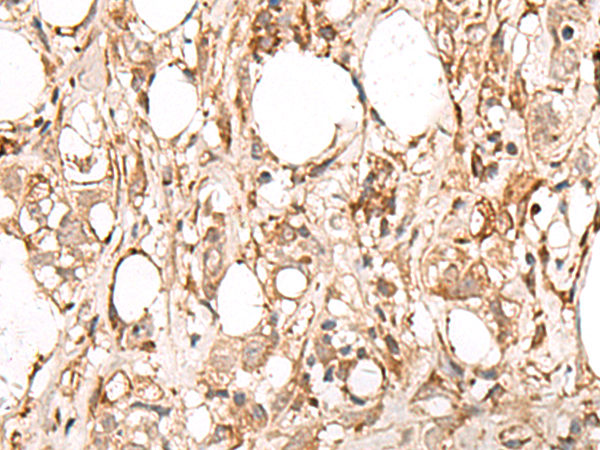

ELISA, IHC |

IHC positive control: |

Human esophagus cancer and Human breast cancer |

IHC Recommend dilution: |

50-300 |